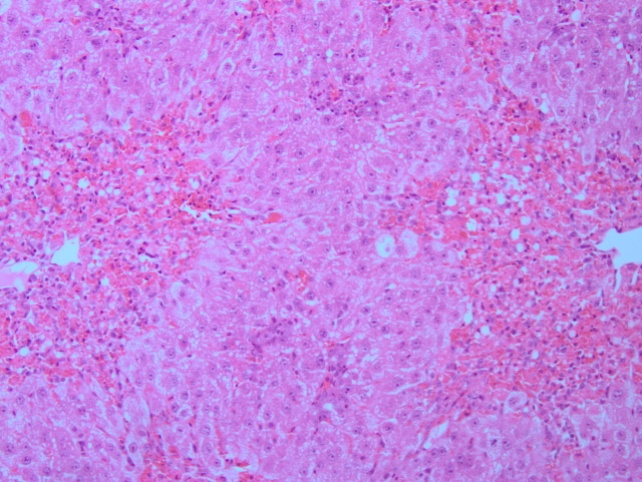

Fig. 3: Effect of M. borneensis on liver histopathological alterations in rats. (A) Saline treated control (B) CCl4 (1.2 ml/kg b. wt.) (C) MB (125 mg/kg b. wt.)+CCl4 (1.2 ml/kg b. wt.) (D) MB (250 mg/kg b. wt.)+CCl4 (1.2 ml/kg b. wt.). Specimens stained with hematoxylin and eosin (a, b, c and d) X 20)

Protective effects of M. borneensis on liver histopathology

The saline control group shows normal liver architecture as indicated in fig. 3 A. CCl4 treated group produced in focal necrosis, dense portal infiltration and inflammation (fig. 3B). Whereas rats treated with M. borneensis showed a minimum grade of necrosis and inflammation (fig. 3 C and D).

The toxicity of CCl4 has caused such extensive vascular degenerative changes and centrilobular necrosis in hepatocytes. Treatment with different doses of ethanolic extract of leaves of M. borneensis produced slightly degenerative changes and lowered the necrotic zones in the hepatocytes, indicating its hepatoprotective efficiency.